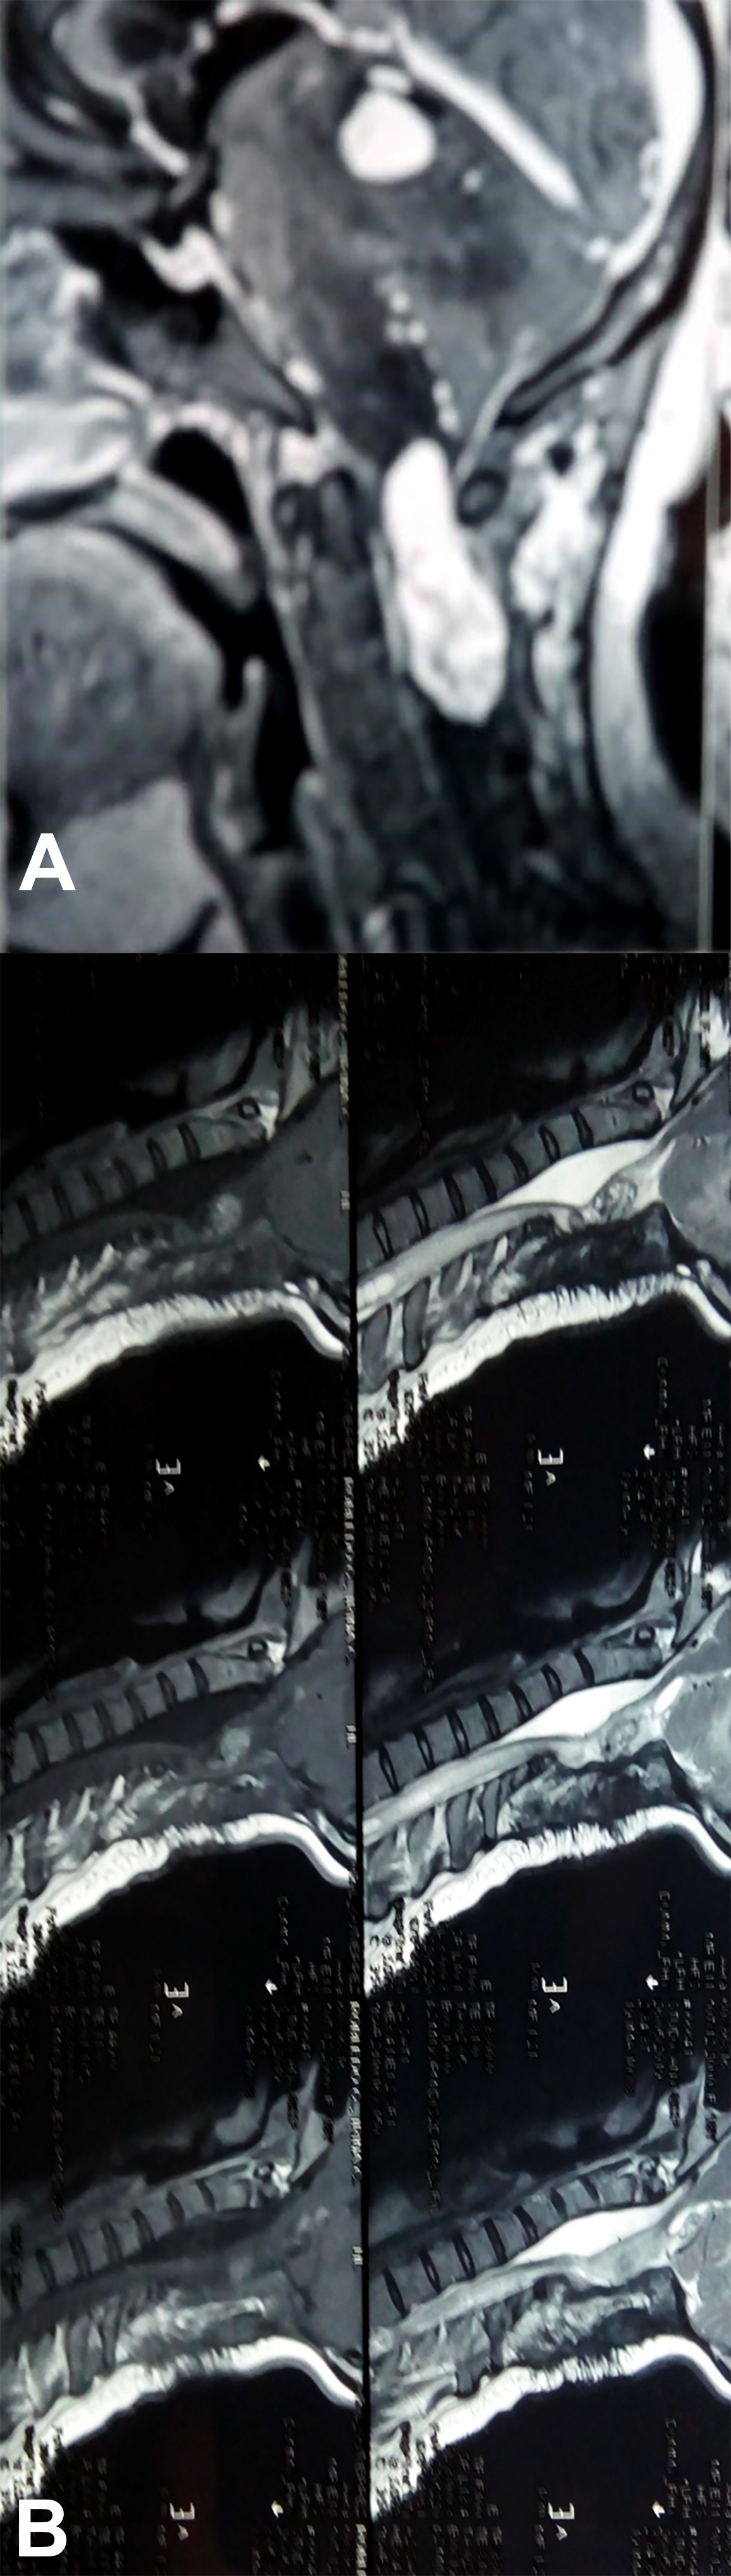

Es evidente que el límite entre el tejido medular y tumoral en las lesiones como los astrocitomas es indiscernible lo que dificulta la posibilidad de resección completa; en los tumores como los ependimomas esta diferencia es más franca y permite seguir un plano de disección seguro (Figuras 3, 4 y 5). Lo anterior condiciona nuestros resultados como han puntualizado diversos autores.5,8 El estado general previo a la cirugía requiere de una valoración juiciosa de las posibilidades de resección. Por ejemplo, el caso 12 (Figura 6) es una paciente portadora de Enfermedad de Von Hippel Lindau, Hemangioblastoma cervical biopsiado en otra institución del exterior del país, fijación de columna cervical y sindrome de Cushing por exceso de medicación corticoidea cuya cirugía debió suspenderse en dos oportunidades por la disminución de su capacidad ventilatoria. Con estos antecedentes y la delgada capa de tejido medular evidenciada intraoperatoriamente se optó por una resección subtotal. A los cuatro meses de la cirugía la paciente recuperó la marcha autónoma y demás parámetros clínicos.

Figura 3: Caso 10. Ependimoma cervical pre operatoria: Lesión sólida C3 y dilatación siringomiélica. Posoperatorio: resección completa, disminución de la cavidad. Restos hemáticos decantados.

Figura 4: Caso 10. Ependimoma cervical. La línea de puntos delimita la pared de la médula del tumor. Nótese la tinción de hemosiderina en la cara ventral medular.![]()

Figura 5: Caso 1. Astrocitoma Pilocítico cervical. A: preoperatoria. B: Cifosis 2 años post resección. Marcada “atrofia” medular.

Figura 6: Caso 12. Hemangioblastoma cervical. Ocupa la mayor parte del cordón medular marcado con círculo.

Respecto del monitoreo intraoperatorio, la utilidad del registro de potenciales evocados, Onda D o Electromiografía dependerá no solo de la obtención de respuestas sino también del diálogo entre el cirujano y el neurofisiólogo,11-13 debido al fenómeno de falso negativo y positivo como se muestra en la Tabla 4. El cirujano recibe la información con retraso al evento y en ocasiones las maniobras de “reanimación” medular (irrigación con suero tibio, corticoides, etc.) no son concluyentes produciendo el abandono de una resección factible. La laminoplastía busca favorecer la restitución del alineamiento espinal, pero debe mantenerse un control, en particular en tumores de la unión cérvico dorsal, sobre el desarrollo o acentuación de escoliosis (Figura 3), en ocasiones presente al diagnóstico y que se acentúa en la evolución posoperatoria.13,16

El caso del Neurocitoma cérvico dorsal (Figura 4), debido a su excepcionalidad, requiere un análisis particular lo cual realizaremos en una comunicación separada.

Figura 7: Caso 6. Astrocitoma Pilocítico cervical. Resección subtotal por caída de PESS. Falso Positivo.

Figura 8: Caso 12. Enf de Von Hippel Lindau. Hemangioblastoma cervical. Se observa otra lesión a nivel del Culmen cerebeloso.